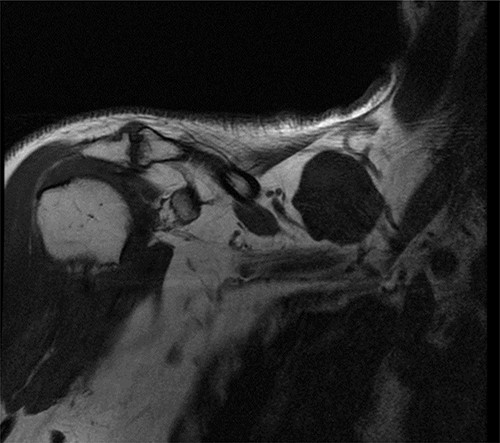

A 54-year-old man presented in clinic for a supraclavicular mass. The patient swam a lot and the mass had been painful for a few weeks. He suffered from hypertension controlled by medications. He had amygdalectomy during childhood and knee-arthroscopy in 2013. Formerly an ultrasonography (US) was performed and revealed a single cystic mass in the right supraclavicular superior and lateral to the brachial plexus and the subclavian vessels, measured at 35 × 17 mm, thin-walled, without associated nodular or tissue formation and without abnormal vascularization. Fine needle aspiration (FNA) was carried out using US and revealed small lymphocyte-like cells mixed with lymphedema-like material. The cyst reccured rapidly after the puncture. Clinically the mass was renitent, moveable and nonadherent. Magnetic resonance imaging (MRI) showed a right supraclavicular cystic formation antero-superior to the subclavian vessels, measured at 43 × 40 × 27 mm, thin-walled, no fleshy component nor associated nodular formation, without tissue enhancement after injection of gadolinium (Fig. 1). A diagnosis of a cystic lymphangioma was retained. A supraclavicular incision was performed under general anesthesia. The cyst was dissected gradually and we ligated and clipped the base of the cyst. The cyst was removed completely (Fig. 2). After hemostasis, a surgical drain was set. The skin was sutured in two layers. There was no postoperative complication. The drain was removed the day after surgery and we discharged the patient at home. The histopathological exams reveal a cystic wall very thinned, bordered by endothelium without any atypical shape and lymphoid tissue without any atypia, confirming the diagnosis of a cystic lymphangioma. No relapse occurred during the follow-up of >3 years.